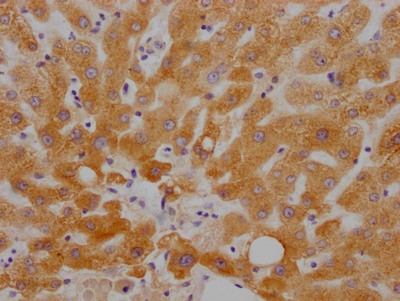

IHC image of CSB-RA784971A0HU diluted at 1:100 and staining in paraffin-embedded human liver tissue performed on a Leica BondTM system. After dewaxing and hydration, antigen retrieval was mediated by high pressure in a citrate buffer (pH 6.0). Section was blocked with 10% normal goat serum 30min at RT. Then primary antibody (1% BSA) was incubated at 4°C overnight. The primary is detected by a Goat anti-rabbit IgG polymer labeled by HRP and visualized using 0.05% DAB.